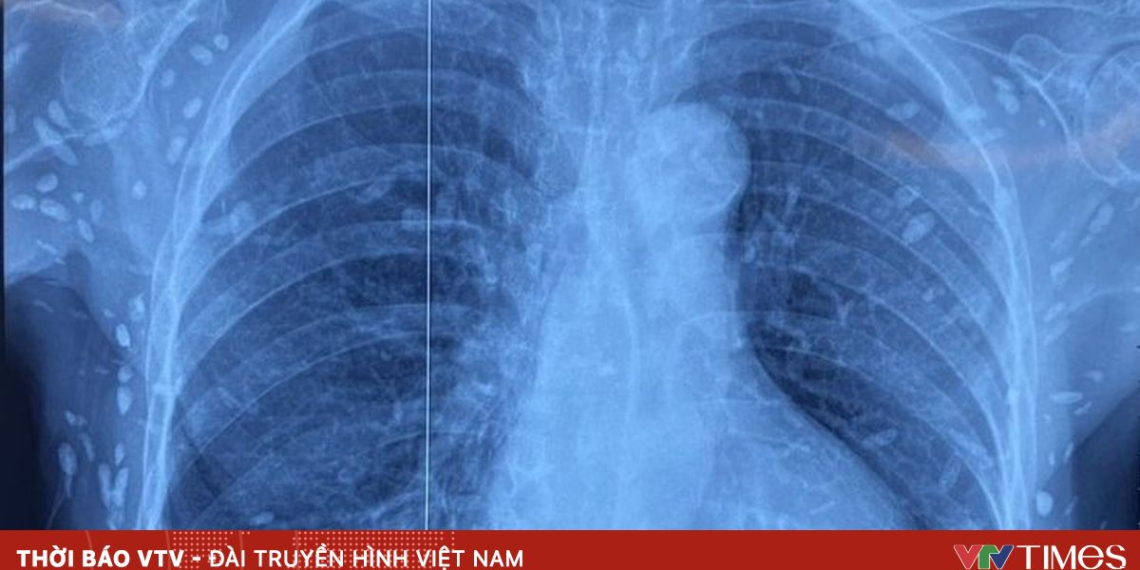

Người bệnh được chuyển đến Viện Lâm sàng các bệnh Truyền nhiễm trong tình trạng rối loạn ý thức, đe dọa suy hô hấp. Kết quả chụp cắt lớp vi tính sọ não và X-quang ngực – bụng cho thấy rất nhiều nốt cản quang nằm rải rác trong nhu mô não và dưới da vùng ngực, bụng, tay. Một số u cục có thể sờ thấy bằng tay.

Theo bác sĩ điều trị, mặc dù xét nghiệm kháng thể IgM âm tính, hình ảnh tổn thương đặc trưng gợi ý người bệnh từng bị nhiễm ấu trùng sán dây lợn (Taenia solium), các nang sán đã vôi hóa và tồn tại lâu dài trong mô. Bệnh nhân được điều trị theo phác đồ, đáp ứng tốt và được cho ra viện tiếp tục theo dõi.